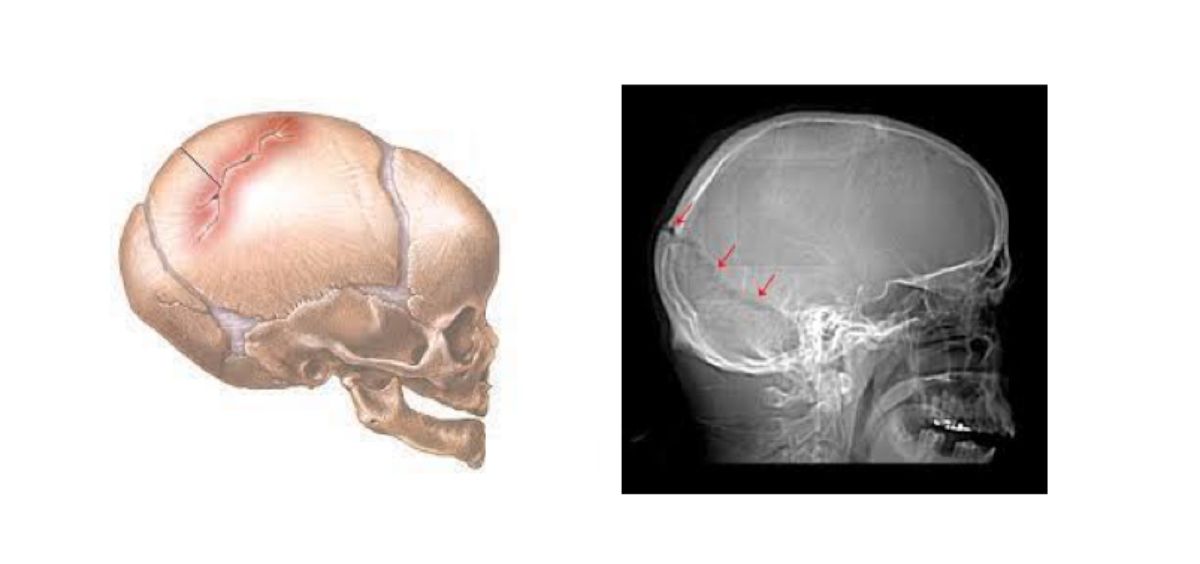

Hay traumatismos craneoencefálicos cerrados, donde no hay heridas en el cuero cabelludo y abiertas, donde hay heridas en la piel del cráneo y fracturas de algún hueso craneal

Según el neurocirujano del Hospital La Luz, “podríamos decir que hay traumatismos craneoencefálicos cerrados, donde no hay heridas en el cuero cabelludo y abiertas, donde hay heridas en la piel del cráneo y fracturas de algún hueso craneal. “También podemos distinguir las que presentan pérdida de conciencia y las que no. Pero lo más importante es que ocurre en el cerebro”.

La mayoría de las fracturas de cráneo van acompañadas de una lesión en el cerebro que puede ser grave o no

Este especialista asegura que la mayoría de fracturas de cráneo van acompañadas de una lesión en el cerebro que puede ser grave o no. Según indica Villarejo, es Importante destacar que las fracturas de cráneo no requieren escayolas, ni férulas, ni inmovilización, pues cicatrizan solas en menos de 6 meses. El problema es que ocurre en el cerebro. Al principio puede haber un hematoma agudo intracraneal que requiere tratamiento quirúrgico para evacuarlo, o puede existir un edema cerebral (hinchazón del cerebro) que requiere una descompresión quirúrgica. “Pero puede ocurrir que el paciente se recupere de un traumatismo por la nieve o por un accidente de tráfico y al cabo de uno o dos meses desarrolle un hematoma subdural (entre la meninge y el cerebro), y que llamamos hematoma subdural crónico. “He tenido la ocasión de operar dos de estos hematomas producidos por golpes esquiando y que desarrollaron este tipo de hematomas, uno era un piloto de aviación de Iberia y el otro un alto ejecutivo. Los dos están muy bien actualmente”, asevera el doctor Villarejo.